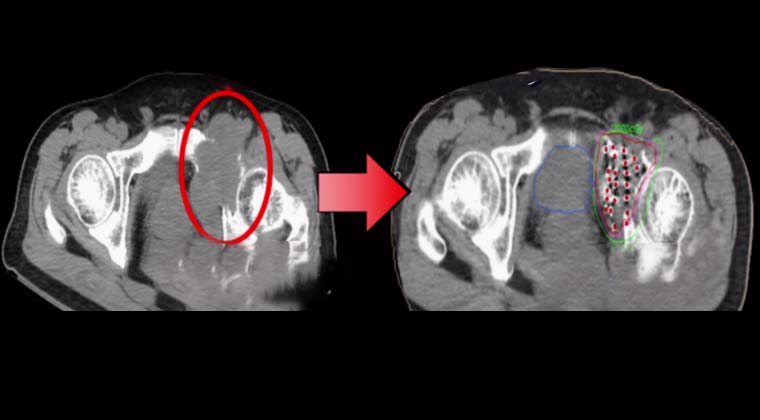

③ Случай 3:

Пациент с раком предстательной железы с костными метастазами. После имплантации частиц I-125 костная опухоль значительно уменьшилась.

Рак предстательной железы с костными метастазами

До лечения

После лечения

После имплантации частиц костная опухоль значительно уменьшилась